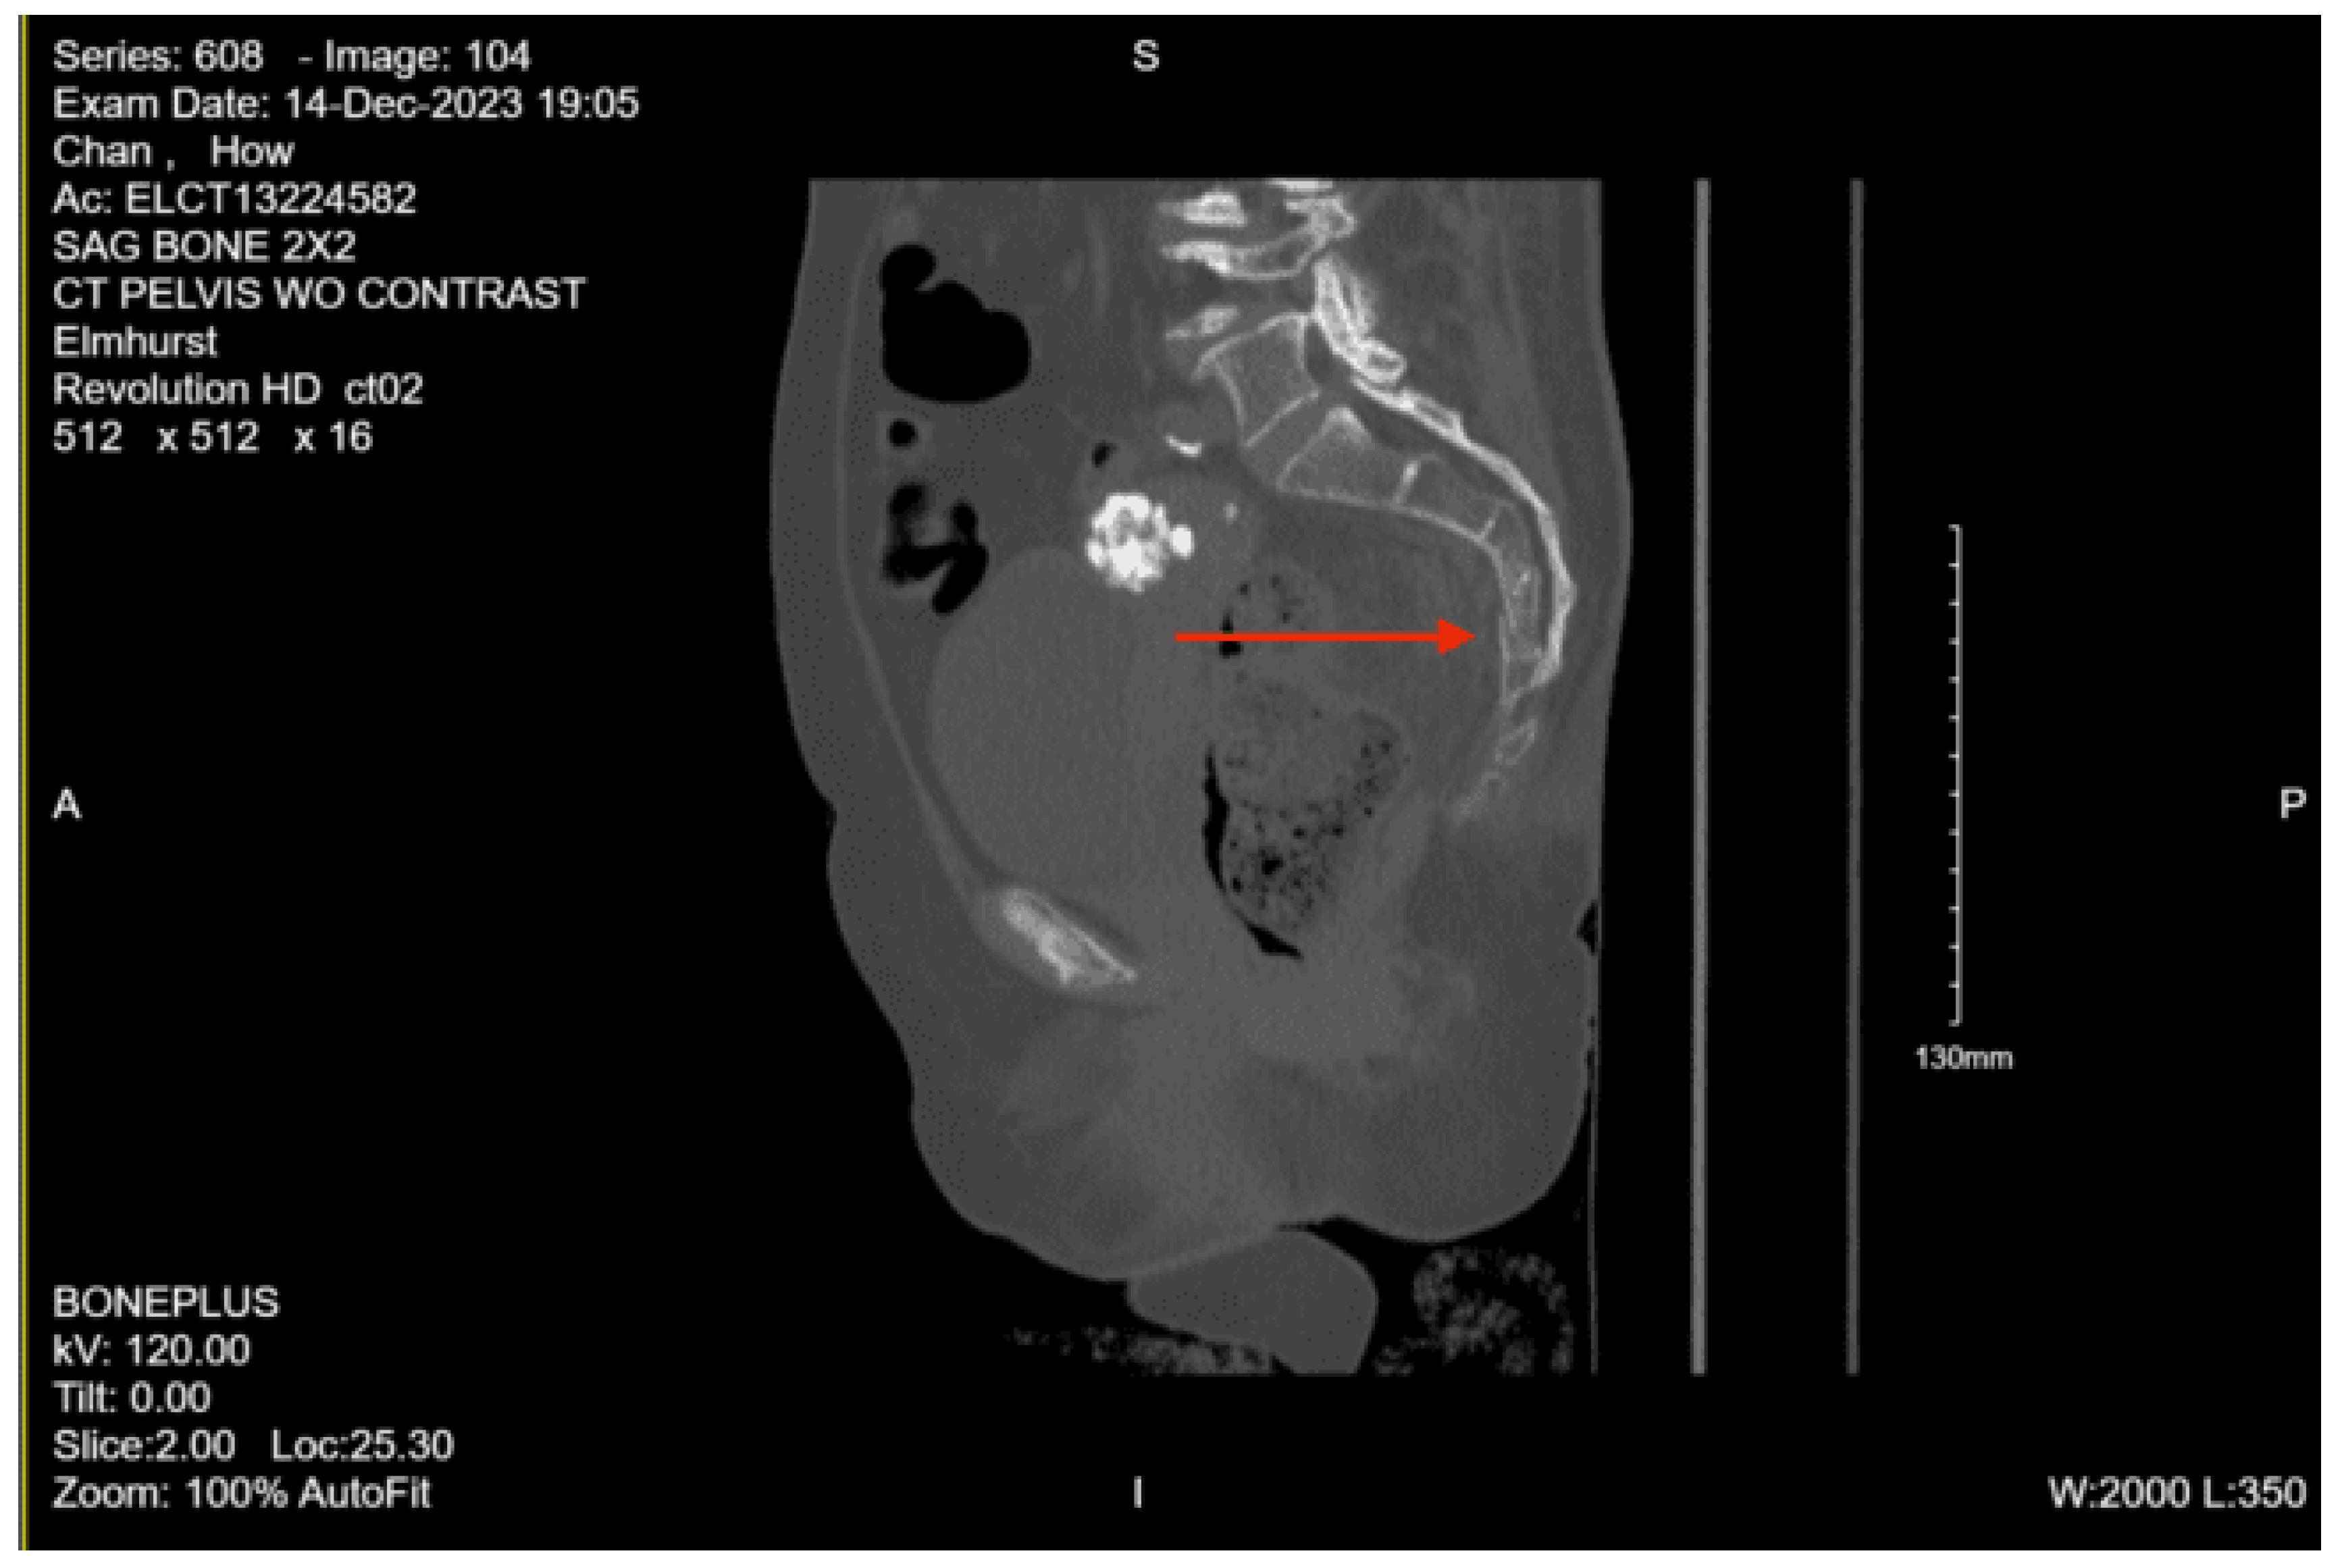

Imaging as shown in Figure 15 and Figure 16:

CT lumbar spine w/o contrast: Nondisplaced sacral fracture, approximately at the level of S4. Deformity at the sacrococcygeal junction, indeterminate chronicity. No other fractures identified. Diffuse osteopenia. Degenerative changes within the lower lumbar spine with grade 1 anterolisthesis of L4 over L5. No acute lumbar spine fractures identified

CT pelvis w/o contrast: Nondisplaced sacral fracture, approximately at the level of S4. Deformity at the sacrococcygeal junction, indeterminate chronicity. No other fractures identified. Diffuse osteopenia. Degenerative changes within the lower lumbar spine with grade 1 anterolisthesis of L4 over L5